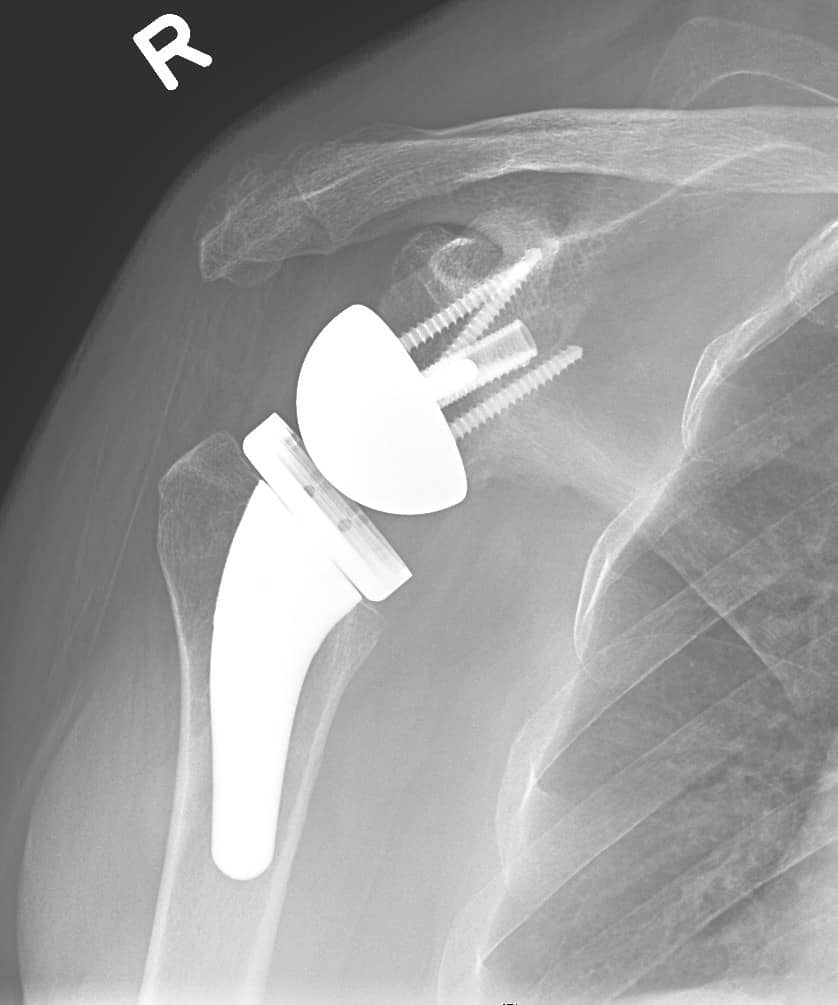

What Is Shoulder Joint Replacement . A shoulder replacement is a procedure that tries to eliminate the source of pain and dysfunction by replacing damaged parts of the shoulder joint with artificial components called prostheses. Whether you have a partial shoulder replacement, an anatomic total shoulder. The specific type of shoulder replacement performed will. The procedure is performed to relieve pain and. Total shoulder replacement, also known as total shoulder arthroplasty, is a procedure where portions of the bones in the shoulder joint are removed and replaced with artificial implants. Shoulder replacement surgery is less common than hip or knee replacements. But more than 50,000 shoulder replacements are done in the. In shoulder replacement surgery, the damaged parts of the shoulder are removed and replaced with artificial components, called a prosthesis. After you have shoulder replacement surgery, rehabilitation is important for a successful recovery. Shoulder replacement surgery involves removing damaged areas of your shoulder and replacing them with artificial parts. After a shoulder replacement, most people experience significant pain relief and improvement in shoulder motion.